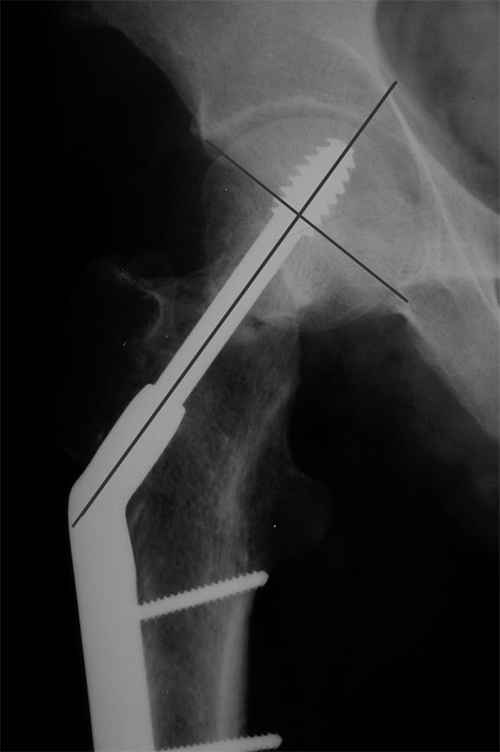

Результат - Псевдоартроз шейки правого бедра (имеются косвенные

признаки разрушения спонгиозной части головки бедра)Планируется -

Работоспособный возраст (43 года).Наиболее приемлемым и реальным

методом лечения предполагается: Удаление конструкций из бедра.

Заполнение полости от винта монолитным аутотрансплантатом из крыла

(крылев) подвздошной кости. Медиализация большого вертела.

Предполагаемый период нетрудоспособности 3-4 мес.